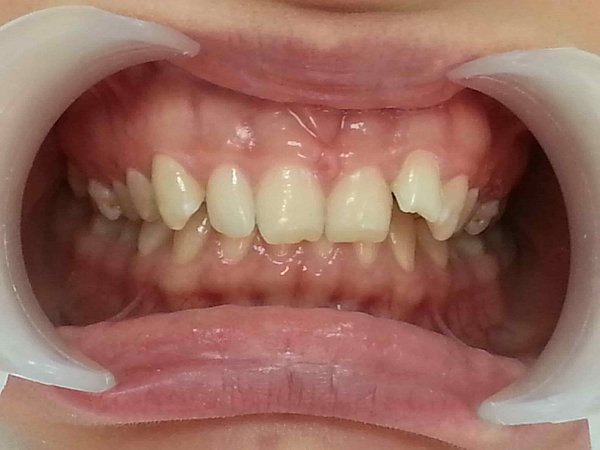

Пациентка 16 лет. Обратилась с жалобой на вертикальную щель между верхней и нижней челюстями.

Объективно: Вертикальная дизокклюзия 4 мм. Перекрестная окклюзия справа, смещение центральной линии нижней челюсти вправо. Щелчок в правом ВНЧС, неправильное положение языка.

План лечения:

1)удаление всех зубов мудрости;

2)устранение вертикальной щели и перекрестной оккклюзии с помощью техники многопетлевой дуги

3)ношение эластических тяг

4)Работа с логопедом для нормализации положения языка.

Достигнуты результаты за 10 месяцев:

1)устраниение вертикальной щели и перекрестной окклюзии справа;

2)выровнена центральная линия нижней челюсти;

3)устранение щелчка в правом ВНЧС;

4)пациентка работает с логопедом для нормализации положения языка.